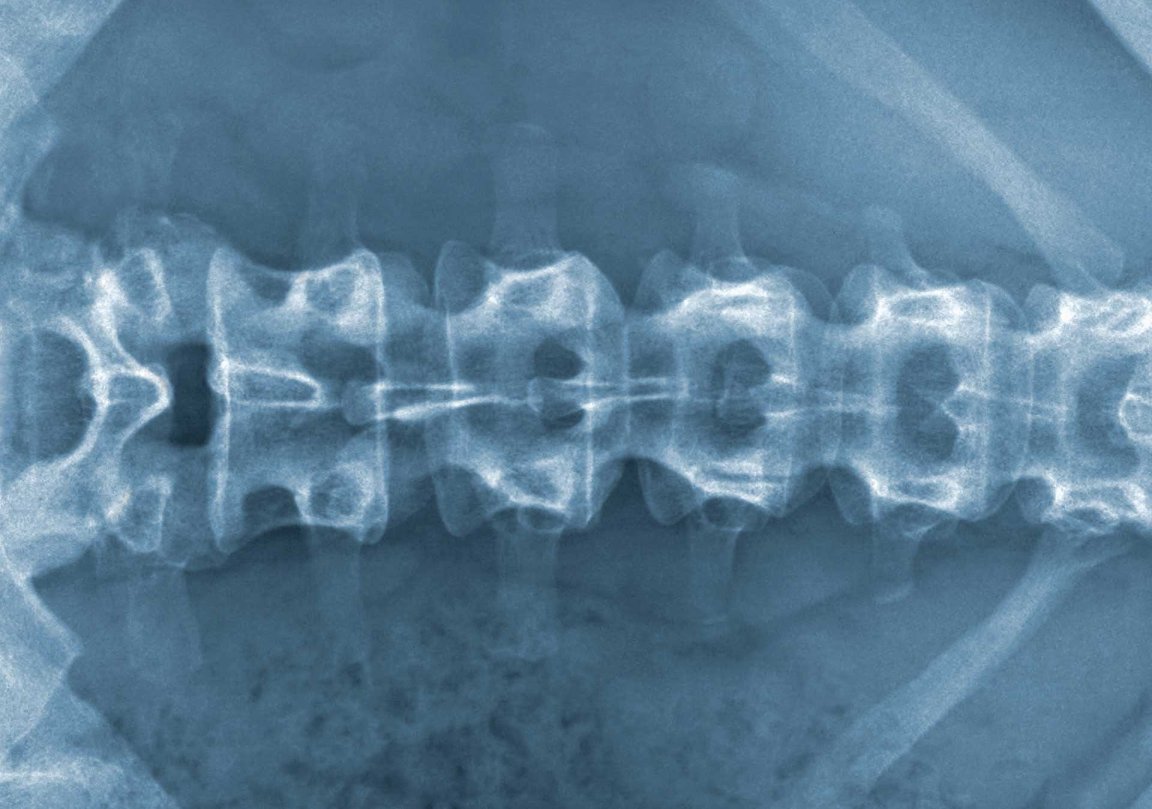

The spine is the point of connection between the brain, sensory neurons (which transmit sensory information such as temperature, pain, and touch), and motor neurons (which control the muscles). At junction point between the spinal cord and both types of neurons, bundles of motor neurons form “motor roots” connecting with the cord, and sensory neurons create similar bundles called “sensory roots.” Traumatic injuries, including severed spinal cords, can tear both motor and sensory roots — when they do, the brain loses control of the connected neurons.

To date, it has been relatively simple for surgeons to implant new motor roots where they were torn, prompting them to reconnect, usually successfully. However, this kind of repair for sensory roots has been more problematic — that is, until this recently developed procedure, in which the original sensory nerve cells are cut and removed from the root and the remaining root itself is placed directly into the spinal cord in a deeper structure.

This area, called the dorsal horn, contains secondary sensory neurons that typically don’t connect directly to sensory roots. However, the technique achieved the return of some spinal reflexes in patients, proving that the implanted neuron did form a functional neural circuit with the spine after all.